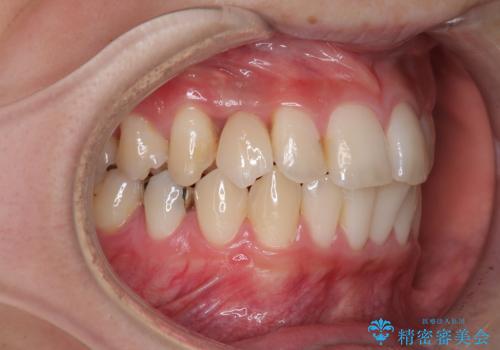

- 前歯の虫歯や治療跡が気になるとのことで来院された患者様です。

以前矯正治療をされ、その時には歯列が整ったので満足されたそうですが、若干の後戻りにより隙間ができ、矯正治療前に治療していた虫歯の跡が気になったため、オールセラミックによる審美治療を希望されました。

目立つ範囲である前歯4歯をオールセラミッククラウンにて補綴することとしました。